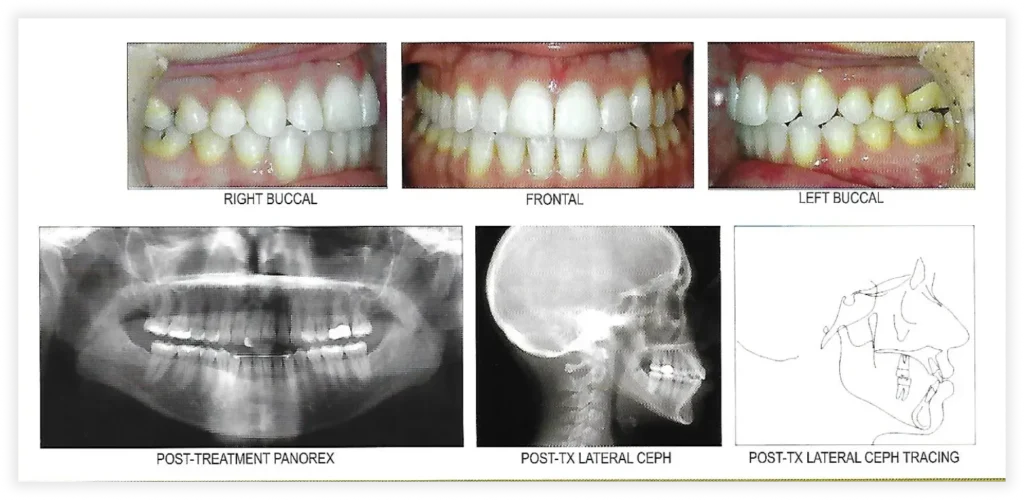

Smile Gallery

Take a look at some of our cases and successful transformations below.

Case #1

Initial Photos

Final Photos